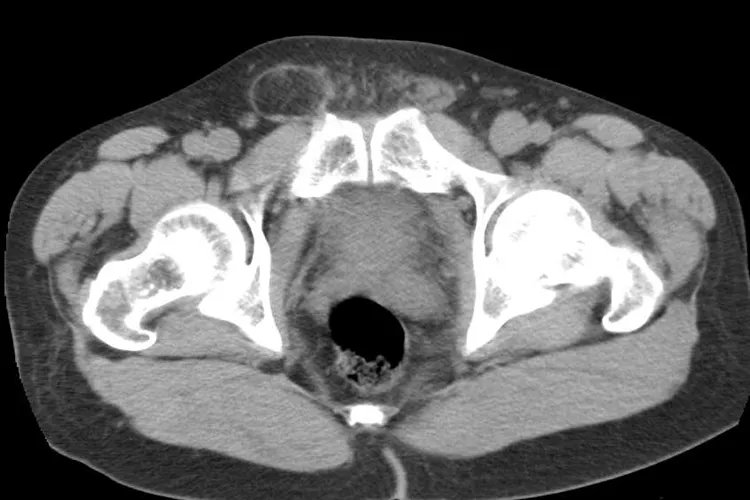

概述疝气鼓包指的是人体中组织或脏器离开了正常解剖位置,在体表形成包块。疝气鼓包是因为存在薄弱点、缺损以及空隙,出现异常的腔内压力增高时,可形成鼓包。症状疝气根据其发生部位分为多种,其中能形成疝气鼓包的常见于腹股沟疝、股疝、脐疝、切口疝。腹股沟疝可分为斜疝和直疝。斜疝基本临床表现是腹股沟区有一突出的肿块。开始时肿块较小,仅仅通过深环刚进入腹股沟管,疝环处仅有轻度坠胀感。当肿块穿过浅环或进入阴囊,即可出现明显的腹部包块。一般包块可回纳,若发生嵌顿疝,则平卧或用手推送不能使疝块回纳,可表现为疝块突然增大,并伴有明显疼痛。

直疝多数表现为直立时在腹股沟内侧端、耻骨结节上外方出现一半球形肿块,并不伴有疼痛或其他症状,平卧位即可消失。

股疝疝块往往不大,常在腹股沟韧带下方卵圆窝处表现为一半球形的突起。平卧回纳内容物后,疝块有时不能完全消失。